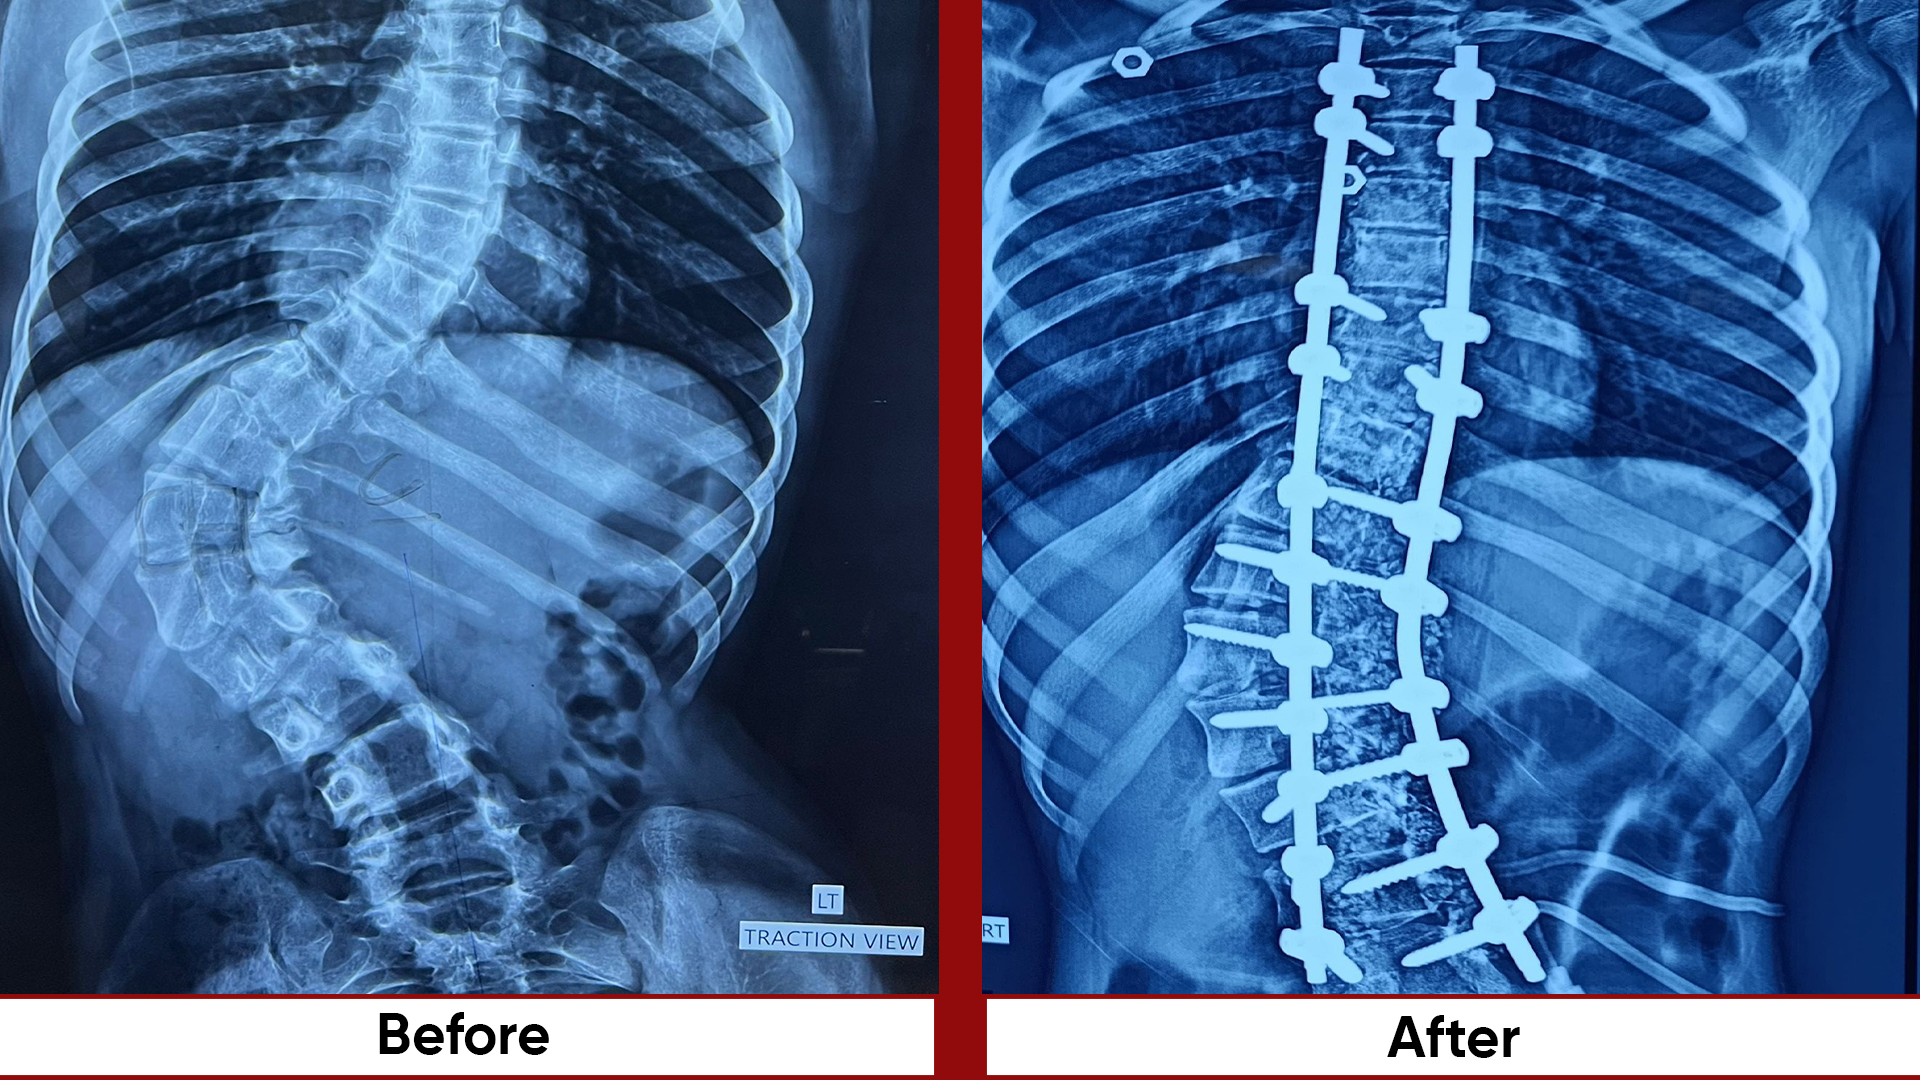

• Fracture Management (simple and complex trauma)

• Deformity Correction (limb lengthening, bowlegs, knock knees)